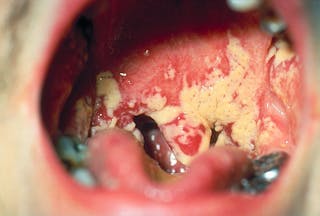

Ma la Candida albicans non passa sempre inosservata. Mentre la maggior parte delle persone portatrici del fungo passerà attraverso la vita senza mai imparare il nome scientifico del loro innocuo inquilino, chiamato anche “commensale”, alcuni lo incontrano come causa comune di mughetto orale, rush da pannolino o infezioni vaginali da lievito. Infatti, il 75% delle donne sperimenteranno almeno un episodio di infezione da lievito nel corso della loro vita.

Peggiora. I cambiamenti nelle difese immunitarie di una persona possono aiutare la Candida albicans a causare infezioni pericolose per la vita nel flusso sanguigno e negli organi interni. I pazienti affetti da HIV/AIDS o quelli sottoposti a chemioterapia del cancro o a trapianti di organi solidi o i bambini con basso peso alla nascita sono a rischio di contrarre questa malattia infettiva. La Candida albicans è l’infezione fungina più comunemente acquisita in un ambiente ospedaliero, in particolare tra i pazienti in unità di terapia intensiva.